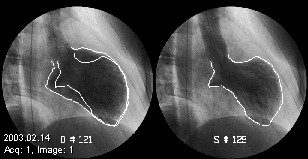

Foto 4. Ventrículo Pre (FEV pre implante)

infarto_miocardio_ventriculo

Foto 5.

Ventrículo Post Implante (FE post)

infarto_miocardio_ventriculo_post_implante